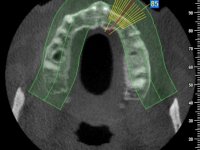

The patient was proposed to undergo a fixed oral rehabilitation consisting of a 2-element bridge over teeth 11 and 21 and a 5-element bridge over 3 implants that would be placed in the location of teeth 22, 24 and 26. The prosthetic structures would have an infrastructure in Zr coated with ceramic and the bridge over the implants would be screwed. The indicated extraction of teeth 25 and 26 and placement of an implant in the 26 site would imply surgery to fill the maxillary sinus. As the patient showed interest in having fixed temporary rehabilitation during treatment, we divided the treatment into 6 phases to achieve this goal: 1- Placement of a temporary bridge over teeth 11,21,25 and 26. With tooth extraction 24. 2- Placement of 2 implants in the location of teeth 22 and 24. 3- Placement of a temporary 6-element bridge over teeth 11 and 21 and over the implants. 4- Carrying out surgery to fill the maxillary sinus. 5 – Placement of the implant in the location of tooth 26 and in the area where the filling of the maxillary sinus was made. 6 – Placement of the definitive work.

A temporary acrylic bridge made in the laboratory with 7 elements was made, with teeth 11,21, 25 and 26 as pillars. The old bridge was removed and tooth 24 was extracted. The provisional bridge after relining was cemented in the mouth. Two implants were placed in the teeth 22 and 24 and 3 months after this intervention an impression was made to make a temporary bridge screwed over the implants and cemented to the teeth. The bridge was placed in the mouth and teeth 25 and 26 were extracted. 3 months later, surgery was performed to fill the maxillary sinus and 6 months later the implant was placed in the location of tooth 26. After osseointegration of this implant, the final impression was made for the final work. The bridge over the implants was permanently screwed on and the bridge over the teeth was cemented with resin-reinforced glass ionomer cement.